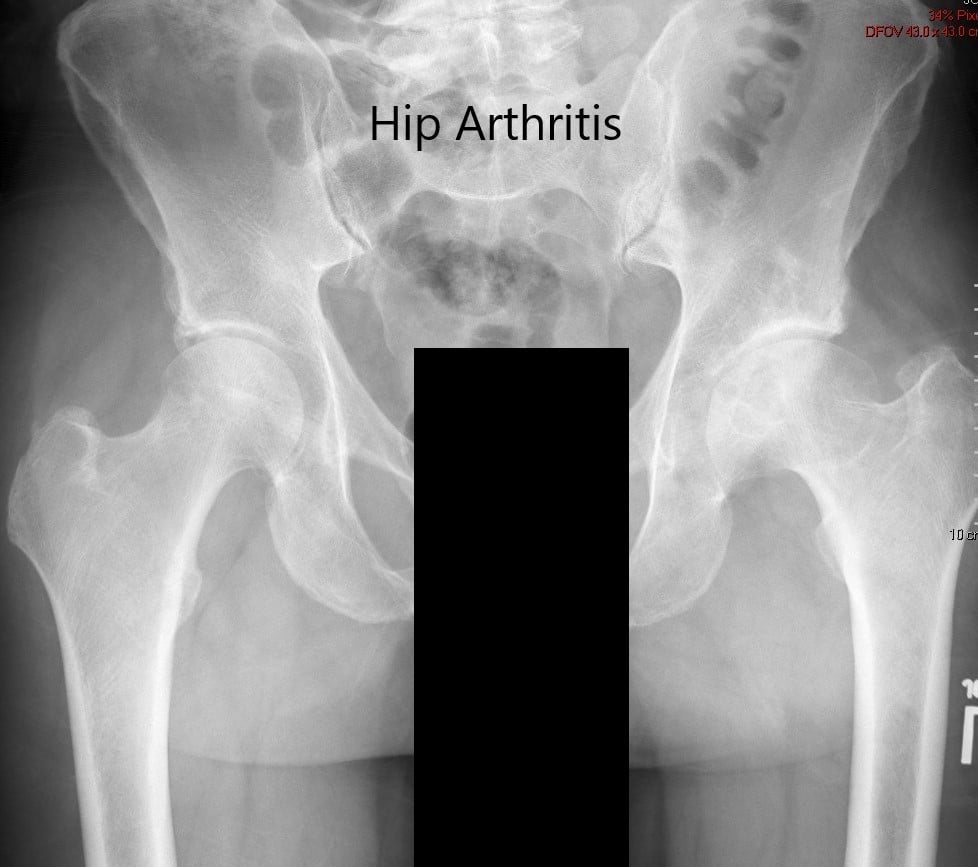

Imaging revealed severe osteoarthritis of the left hip with subchondral cysts, sclerosis, and osteophytes. The left acetabulum was shallow with a shortened left femoral neck.

Preoperative X-ray of the pelvis showing AP view of the pelvis with both hips.